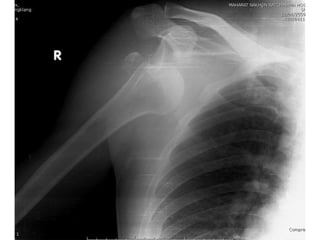

 Flim right shoulder AP , transcapular หลัง CR

Treatment  Closed reduction Pain control : pethidine 1 amp iv stat  Sedation : valium 1 amp iv stat  Traction-countertraction  Interlocking arm sling  Flim right shoulder AP , transcapular หลัง CR  F/U 2 week

investigation  Film rightshoulder AP , transcapular  Film right humerous AP , lateral

Imp : Right anteriorshoulder dislocation with avulsion fracture right greater tuberosity